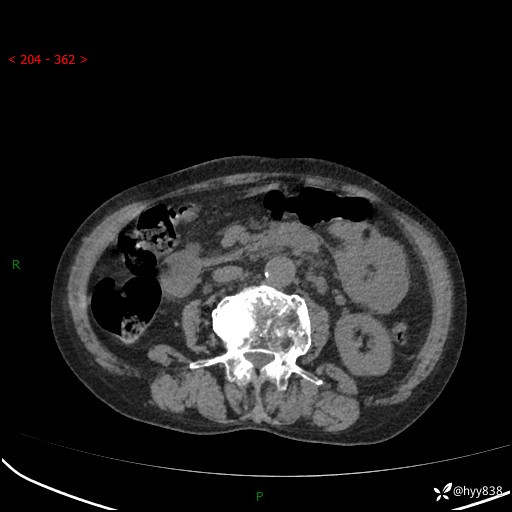

全腹部CT平扫